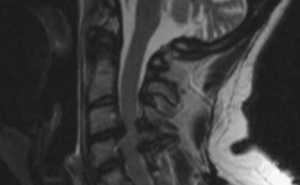

Изображения, полученные с помощью вышеописанной последовательности T1-vibe без жироподавления, открывали в программе InobitecPro в режиме мультипланарной реконструкции, где строились аксиальные срезы, параллельные в коронарной и сагиттальной проекциях нижним замыкательным пластинкам L3-, L4-, Ь5-позвонков (рис. 1). На построенных изображениях на всех 3 уровнях с помощью инструмента «ROI полигон» обводили многораздельные мышцы с обеих сторон, как показано на рис. 2 (вдоль границы остистого и суставного отростков, затем по фасции многораздельной мышцы), для оценки средней интенсивности сигнала и площади выделенной зоны. Кроме того, в режиме T1-vibe без жироподавления с помощью инструмента «ROI овал» измеряли среднюю интенсивность сигнала в жировой клетчатке слева от паравертебральных мышц (см. рис. 2).